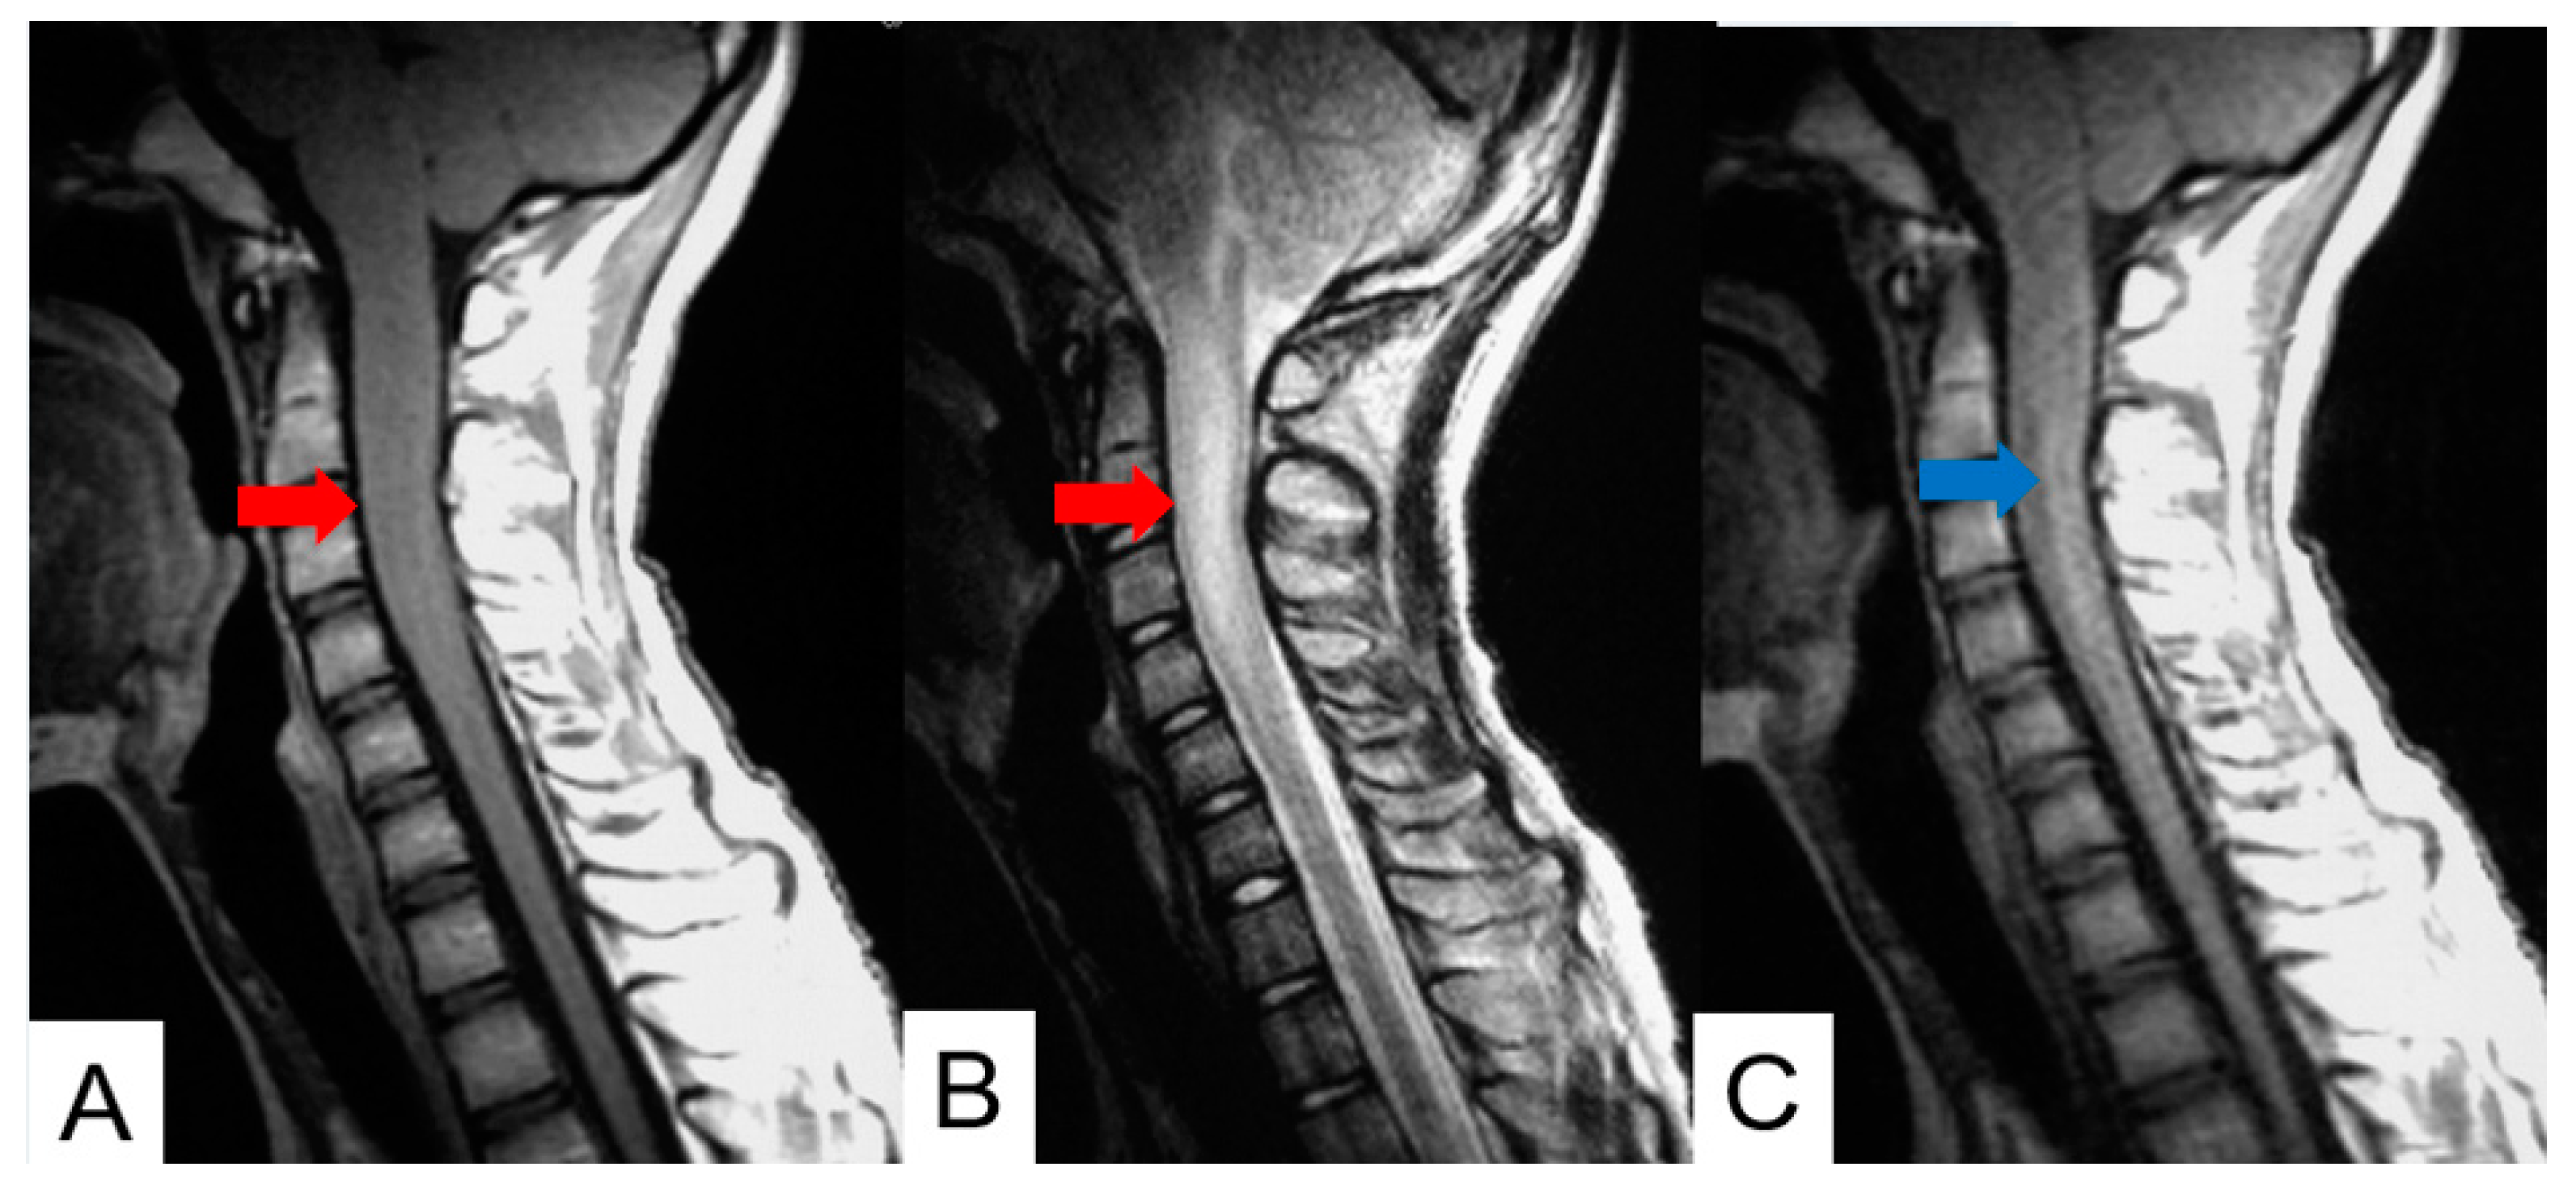

- Jung, J.S.; Choi, Y.S.; Ahn, S.S.; Yi, S.; Kim, S.H.; Lee, S.K. Differentiation between spinal cord diffuse midline glioma with histone H3 K27M mutation and wild type: Comparative magnetic resonance imaging. Neuroradiology 2019, 61, 313–322. [Google Scholar] [CrossRef] [PubMed]